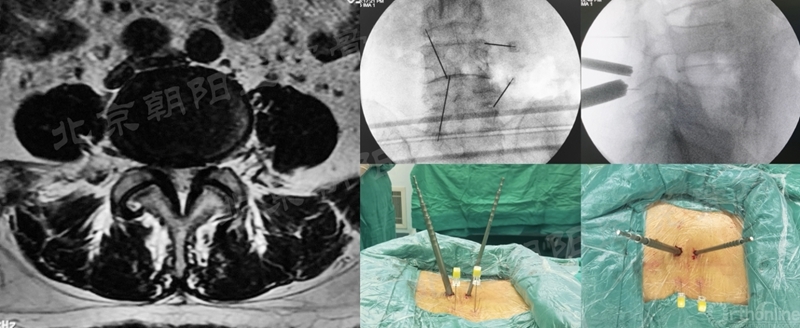

2、 镜下迷失——节段错误

#14例UBE,术中迷路,L5/S1突出做到了L4/5右侧透视图),及时转开放减压。

本例手术镜下迷失原因总结:

① 术前设计切口靠近端,本期望利于椎板钳减压椎板,弄巧成拙;

② 定位后通道方向没有记牢,操作时角度改变了;

③ 做L5/S1体位摆放应注意把上半身摇高,使L5/S1水平;

透视正位应将L5/S1间隙标准化,否则定位不准;

⑤ 患者肥胖,脂肪软组织厚;

⑥ 镜下结构不对马上透视。